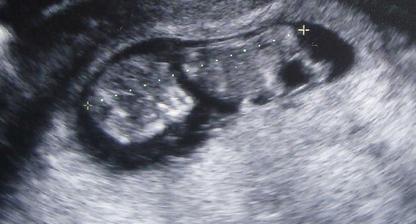

8.4. 11+3 mimis ma 4.13cm

21.4. nt screening ....vse ok ....cekani na krev

Velky Uz v podoli 10.6. nedopadl nic nejen ze nechtel ukazat mimous co je zac, ale mel dve cysty na mozecku

24.6. kontrola dopadla dobre cysty se vstrebavaji a je to KLUK!!! vazi 455g prej je drobnejsi 🙂)